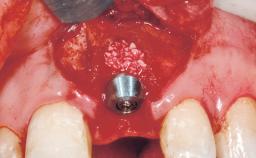

Immediate Placement of an Implant in a Maxillary Right Central Incisor Site

A 30-year-old female patient was referred to the office for the treatment of tooth 11. Her chief concern at the initial visit was to inquire, “Why is my tooth pink?” Upon clinical examination, it was determined that tooth 11 had a previous history of trauma and that the clinical crown had become noticeably pink in color as a result of internal resorption. This diagnosis was confirmed radiographically, indicating a large radiolucency involving the central and distal portions of the clinical crown. It was determined that restoration of this tooth was not possible, and that extraction was indicated. The presence of a mid-line diastema, which the patient wanted to reproduce, directed the treatment plan for tooth replacement utilizing a dental implant.

| Placement Protocol | Immediate implant placement |

| Socket Morphology | Single-root socket |

| Socket Integrity | Sufficient, with intact bone walls |